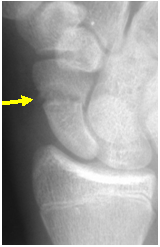

You need a scaphoid

view to be certain!